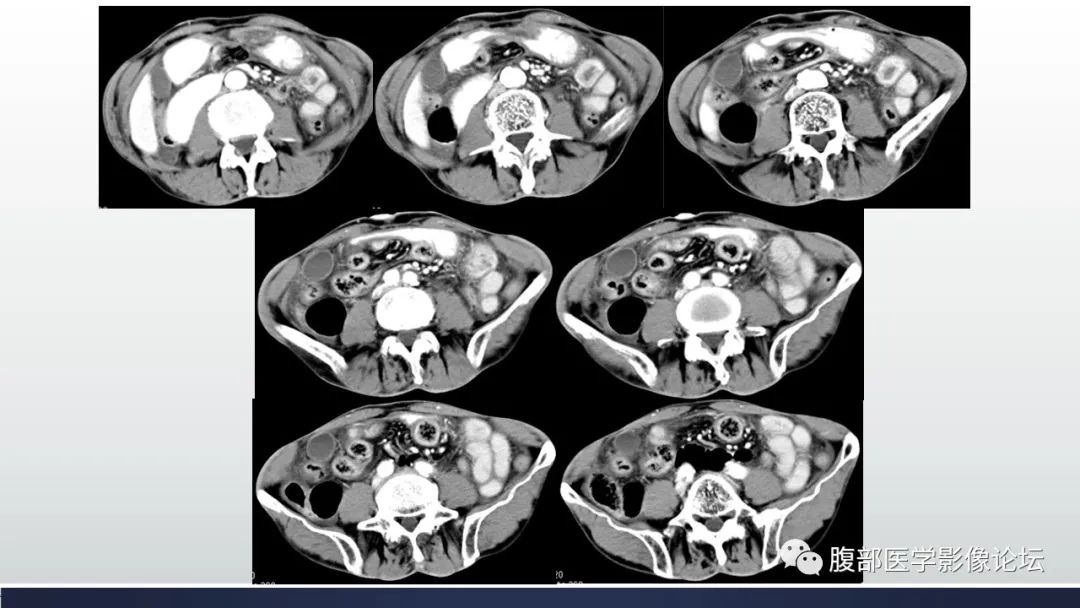

腹内疝征象:肠管异位征象、肠梗阻征象、占位征象、鸟嘴征(疝口处肠管受压呈鸟嘴状狭窄)、缆绳征或漩涡征(肠系膜及血管牵拉、纠集、移位并充血水肿)绞窄性小肠梗阻征象:1直接征象,肠系膜血管闭塞、不强化,肠系膜水肿呈云雾征;2间接征象,肠壁明显增厚呈靶征,肠壁强化不均、弱强化或不强化,肠腔血性渗液,肠壁、肠系膜出血;3并发症征象,肠壁间、肠系膜积气征、肠系膜静脉或门静脉气栓征、腹水或气腹。§十二指肠旁疝 据文献报道,此型为最常见类型,约占全部内疝的53%。与其他类型内疝不同,十二指肠旁疝的发生有性别倾向,男4性发病率约为女性的3倍。包括左侧及右侧两种亚型,其中前者常见(约占3/),二者临床表现相似,均为先天性疝,有疝囊,但胚胎学发育病理基础却不同。 医学百科网 | YxBaike.Com